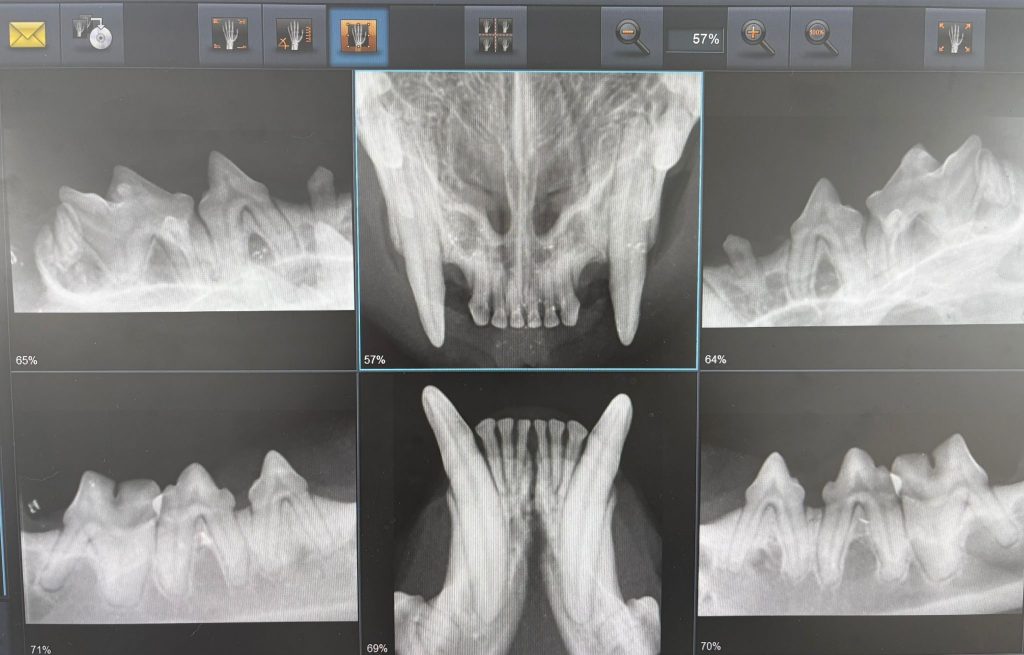

Dentalröntgen / Zahnbehandlungen

Eine digitale Röntgendiagnostik ist gerade bei Katzenzähnen eigentlich unverzichtbar. Vereinbaren Sie gerne einen Termin für eine professionelle Zahnreinigung, oder Zahnsanierung. Wir bieten die Erfassung des Zahnstatus gerne mit an.